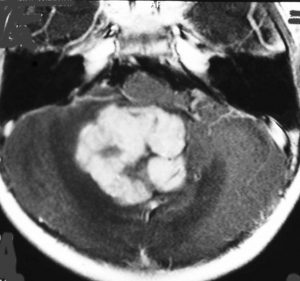

典型的な小脳虫部(小脳の真ん中)の髄芽腫です。横の方,ルシュカ孔へ伸びていないので上衣腫と区別できます。ガドリニウムという造影剤で白く写っています。